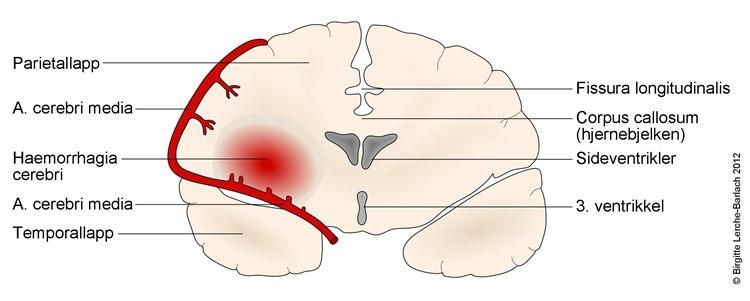

- I de aller fleste tilfeller vil årsaken til lammelser være et hjerneslag med sviktende blodtilførsel til deler av hjernen på grunn av en blodpropp (85 prosent) (danner et hjerneinfarkt), mens årsaken sjeldnere (15 prosent) er en blødning fra blodkar i hjernen

- Tilstanden kan oppstå i løpet av sekunder (eks. blodpropp fra hjertet), minutter (vanligvis hjerneblødning) eller minutter til timer (blodpropp som dannes lokalt i et kar i hjernen, trombose)